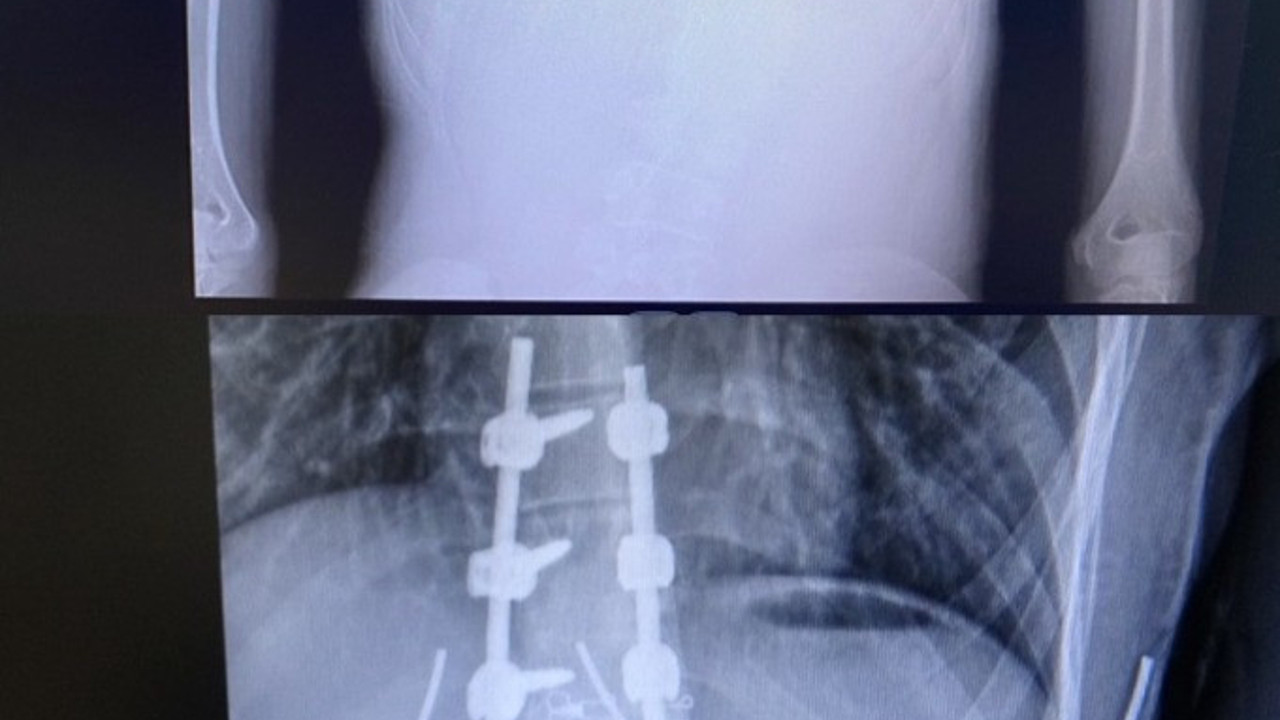

Ulusoy, “Hastamız 15 yaşında bize bel eğriliği ile 1 kez ameliyat olmuş şekilde başvurdu. Muayenesini yaptığımızda belindeki vidaların bir kısmının gevşediğini ve belindeki eğriliğin aynı şekilde ameliyat öncesi haline döndüğünü gördüm. Ameliyatını planladık ve başarılı bir şekilde gerçekleştirdik. Tekrardan implantları yenilendi ve eğriliği düzeltildi, şu an için ameliyattan sonraki birinci ayımız hastamız sıkıntısız bir şekilde yürüyor herhangi bir problemimiz yok" dedi.

“Sağlık Bakanlığına bağlı kamu hastanelerinde Güneydoğu Anadolu Bölgesinde yapılan ilk revizyon ameliyatı. Hastanın doğuştan skolyozu vardı. Bizim gördüğümüz 3 yıl önceki grafilerinde artık ameliyatlık hale geldiği görülüyor zaten. 2 yıl önce dış merkezde bir operasyon geçirilmiş, sonraki dönemde komplikasyon gelişmiş, içeriye konulan sistem gevşemişti. Skolyoz; doğuştan gelen bir hastalık daha çok çocukluk döneminde görülmekte, ameliyatla düzeltilmez ise şekil bozukluğu kalıcı olur. Skolyoz tedavisinde olumlu sonuç alınabilmesi için tedavi sürecinin çocukluk döneminde başlaması gerekli olup nihai ameliyatlarla da 14-15 yaşlarında başarılı bir şekilde sonuç bulunmaktadır. İlerleyen yaşlarda tedavi zorlaşarak istenen sonuç elde edilemeyebilir”